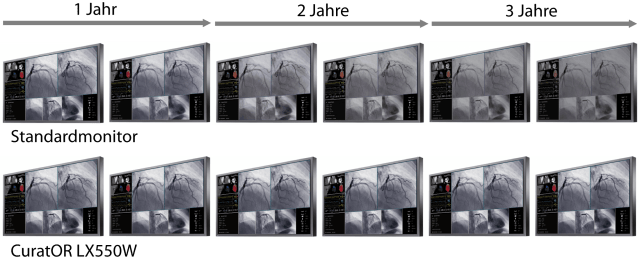

Der 55" Breitbild-Monitor mit 4K UHD Auflösung ist ideal für die Anzeige medizinischer Bilder in der Angiographie, Kardiologie oder Endoskopie geeignet und kann sowohl an der Wand als auch an eine Deckenhalterung montiert werden. Das Sicherheitskonzept und die langlebige Hintergrundbeleuchtung sind ideal für einen langfristigen, stabilen und verlässlichen Einsatz.

- Großer Blickwinkel durch IPS LCD Technologie.

- Optimale Anzeige von DICOM Bildern durch Graustufenabgleich nach DICOM Part 14 Standard ab Werk.

- Einheitliche Helligkeitsverteilung über den gesamten Schirm.